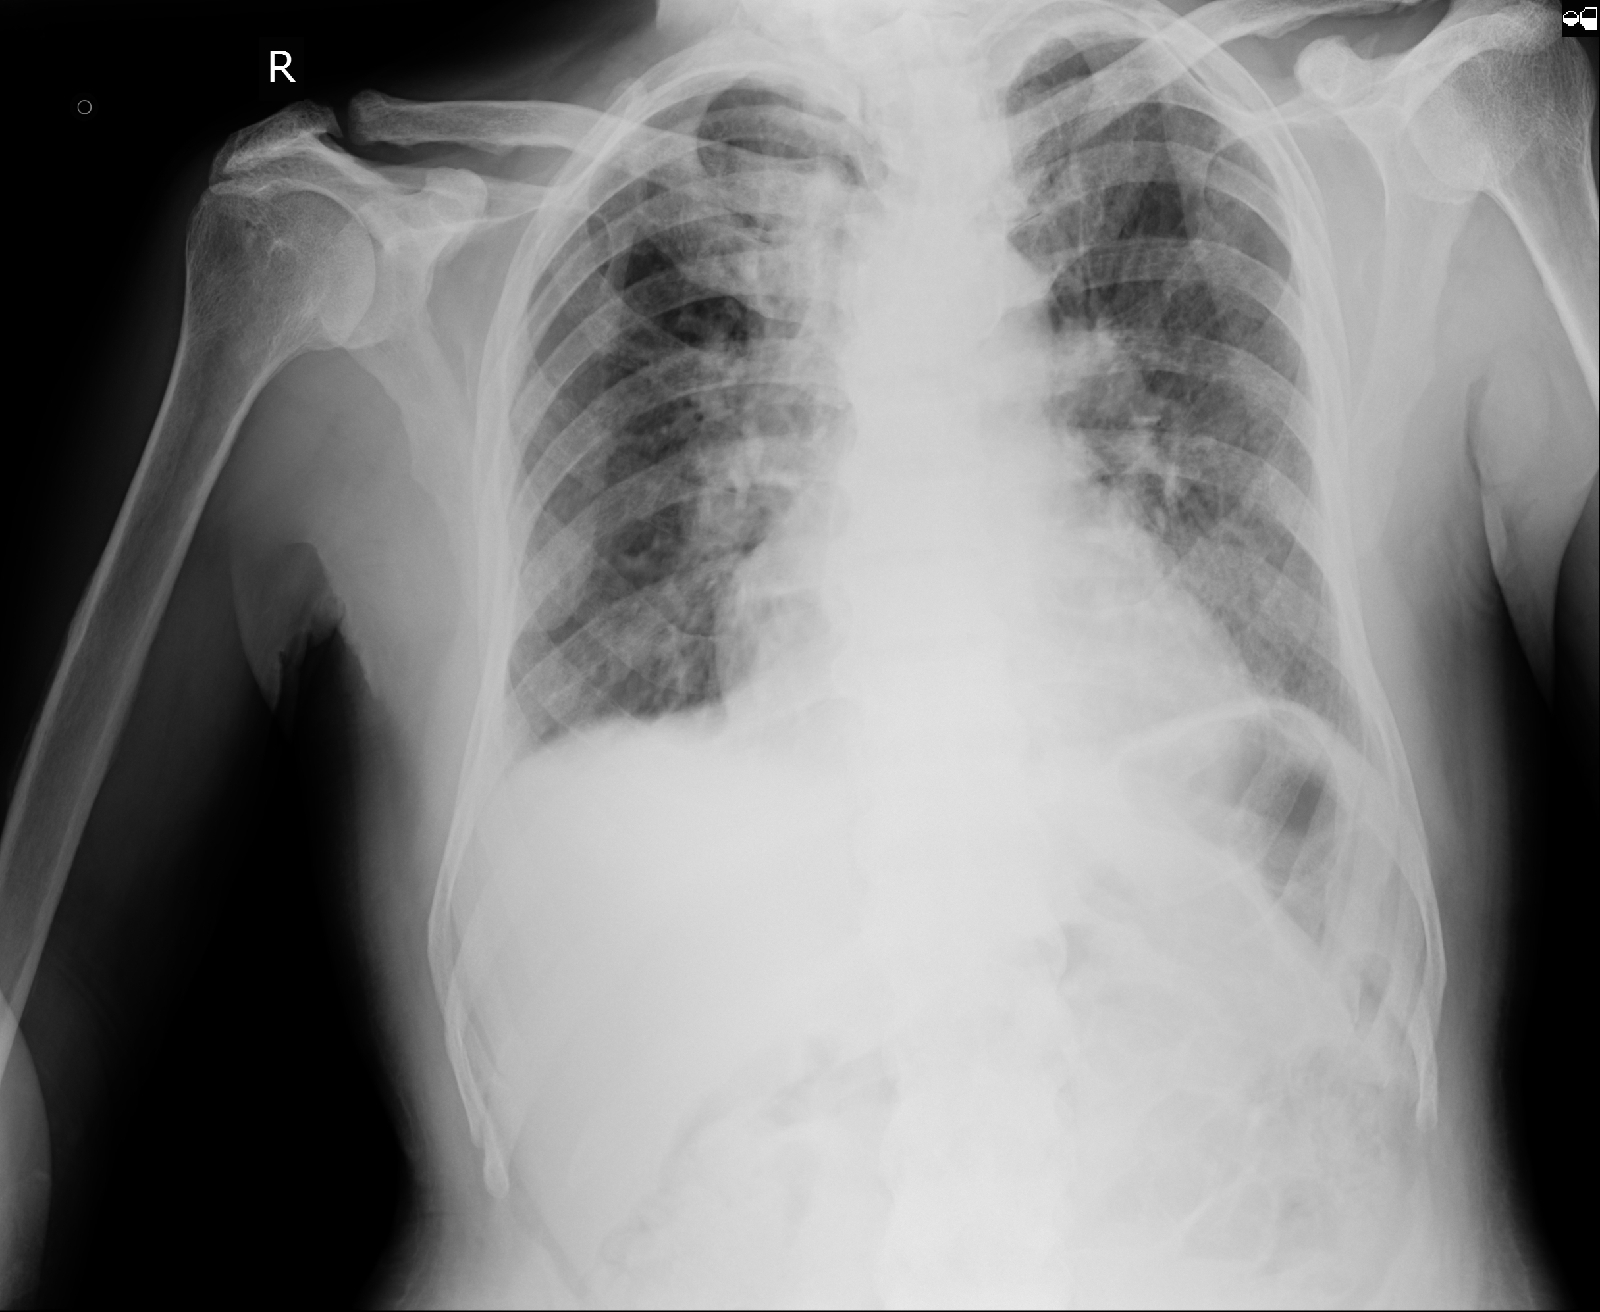

Radiological Investigations:

-US Abdomen shows Bilateral grade II Chronic Kidney Disease with bilateral simple renal cortical cysts

Cardiac Work up: